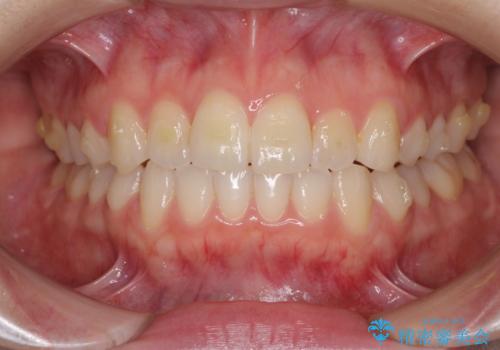

前歯のクロスバイトをインビザライン矯正で改善

- 前歯のデコボコと上下のクロスバイトを気にして来院された患者様です。

インビザラインを用い、IPR(歯と歯の間を削る)と歯列全体を拡大させることで、歯並びを整えていくこととしました。

上の前歯が下の前歯を乗り越える際、奥歯がほとんど咬めない時期があり、乗り越えた後も、インビザライン特有の奥歯の咬みにくさが続きました。

咬み合わせ改善のために治療期間を要しましたが、最終的に奥歯はしっかりと咬めるようになりました。